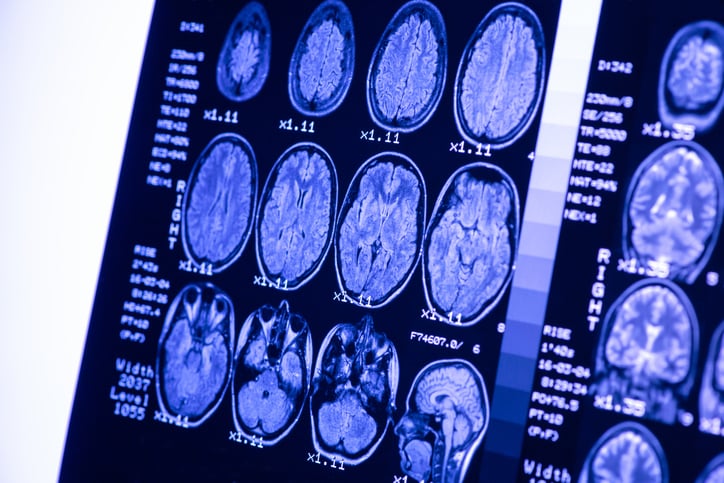

I tumori del sistema nervoso centrale rappresentano ancora una grande sfida per la medicina e la ricerca scientifica: ogni anno, circa 6000 italiani ricevono una diagnosi di tumore al cervello. Tra questi, il glioblastoma è uno dei più diffusi; nel 70% dei casi colpisce persone tra i 45 e i 70 anni di età, ma può presentarsi anche nei bambini. Il glioblastoma multiforme rappresenta il 15-20% di tutti i tumori pediatrici a carico del sistema nervoso centrale. Nonostante i recenti progressi in campo medico, il glioblastoma al momento è uno dei tumori più aggressivi nell'uomo e, ad oggi, non ci sono terapie davvero efficaci per la sua cura. C’è una grande urgenza di trovare approcci terapeutici mirati ed efficaci, e per farlo occorre prima capire i meccanismi molecolari che guidano la nascita e lo sviluppo di questo tumore. Simona Camorani è una giovane ricercatrice napoletana che, dopo essersi laureata in Biotecnologie mediche e aver conseguito un dottorato di ricerca in Oncologia e Endocrinologia molecolare all’Università Federico II di Napoli, sta continuando la sua ricerca sul glioblastoma nella città partenopea all’Istituto per l'endocrinologia e l'oncologia sperimentale "Gaetano Salvatore" del Cnr.

«Lavoro sul glioblastoma: in particolare, sto studiando un meccanismo molecolare tipico di queste cellule maligne, guidato dalla proteina EGFR. Essa è presente in grande quantità sulla superficie delle cellule di glioblastoma; circa la metà dei tumori ne esprime anche una forma mutata, EGFR-vIII, responsabile di una maggiore aggressività della neoplasia. Quando si colpisce il glioblastoma con farmaci diretti contro questa proteina mutata, il tumore per difendersi reagisce aumentando un’altra proteina, PDGFR?, innescando un meccanismo compensatorio che ne sostiene la sopravvivenza».

«Esattamente. Il mio progetto si propone proprio di sviluppare una terapia innovativa basata sul trattamento combinato delle cellule di glioblastoma con piccole molecole di RNA artificiali, chiamate aptameri, in grado di bloccare le proteine EGFRvIII e PDGFR?. In questo modo le cellule di glioblastoma dovrebbero essere più deboli e sensibili ai trattamenti chemioterapici convenzionali. Abbiamo già ottenuto alcuni risultati preliminari pubblicati sulla rivista scientifica Oncotarget e questo ci incoraggia a proseguire su questa strada».

«Siamo ancora molto lontani dal poter dire di aver trovato un nuovo trattamento per il glioblastoma: siamo appena alla fase in vitro, ma i nostri studi possono aprire nuove prospettive di terapia molecolare mirate per il glioblastoma e per i tumori maligni del cervello ad oggi ancora difficili da curare».